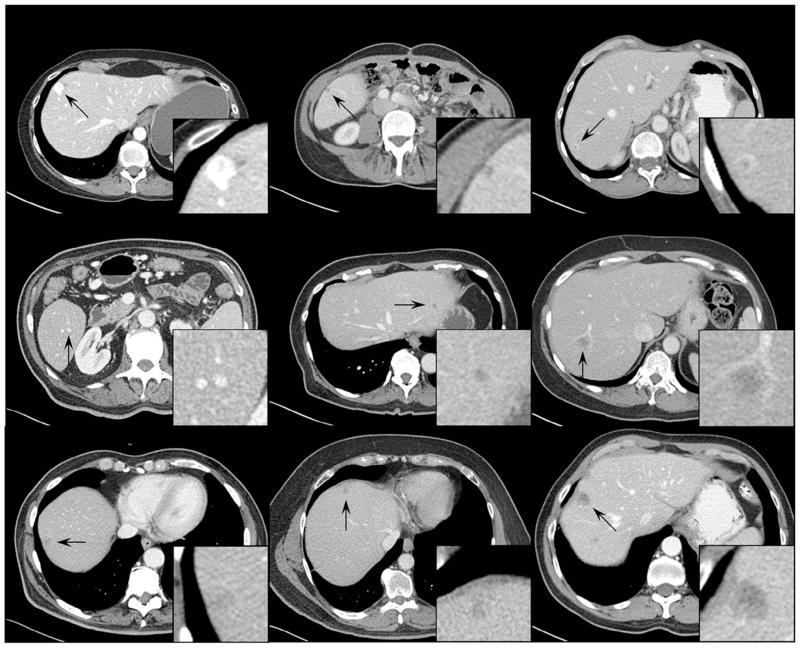

- (a)–(f) show the original liver lesions

- (g)–(l) show the inserted liver lesions

- 不同扫描条件下肝脏病灶的结果(全图+放大图)